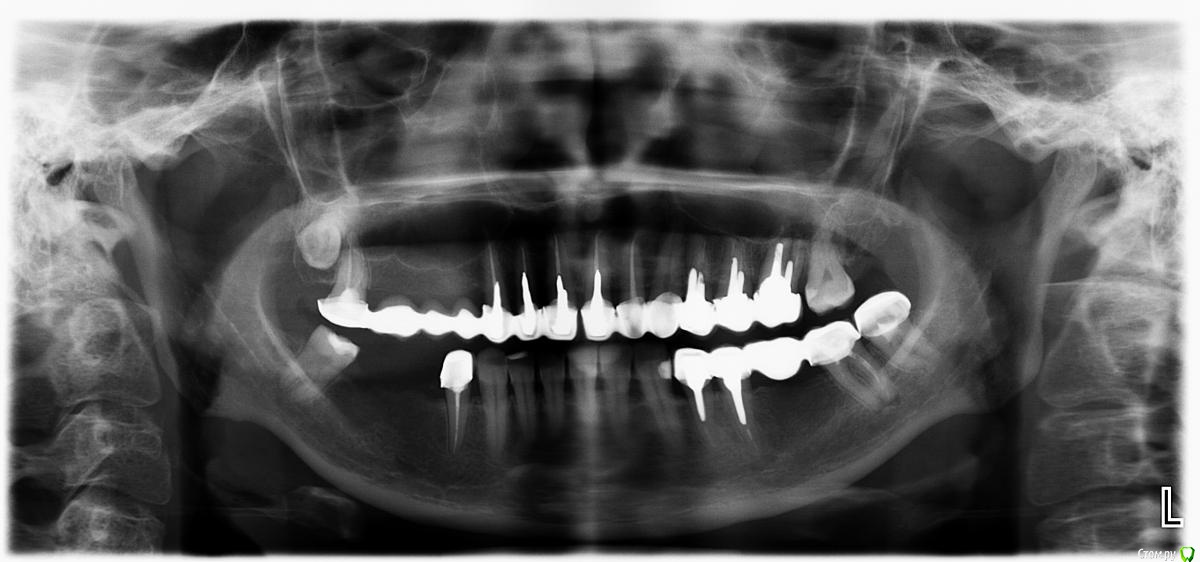

sabik Опубликовано 13 марта, 2019 Поделиться Опубликовано 13 марта, 2019 Хотела б услышать мнение по поводу возможности установки имплантов, ходила в несколько клиник, все говорят разное, общее только то, что на КТ видно, что нет кости вообще, проблема с верхней пазухой,нужна операция лор, еще вопрос можно ли повторить этот мост наверху при отсутствии трех зубов? Не хотят браться за меня нигде Еще беспокоит тупая ноющая боль время от времени, на снимке слева внизу, причину не находят. Подскажите, есть ли зубы на удаление, и какие проблемы видно в общем? Ссылка на комментарий

sabik Опубликовано 14 марта, 2019 Автор Поделиться Опубликовано 14 марта, 2019 Болтается мост сверху, на снимке слева, и беспокоит тупая боль снизу на этой же стороне, жую почти 2 года другой стороной, нужно менять коронки и где возможно установить импланты. Хочу услышать мнение профессионалов по снимку, что можно сделать в моей ситуации. По КТ кости не хватает нигде. Ссылка на комментарий

Бендер Опубликовано 14 марта, 2019 Поделиться Опубликовано 14 марта, 2019 Выглядит небезнадежно кстати 2 Ссылка на комментарий

sabik Опубликовано 23 марта, 2019 Автор Поделиться Опубликовано 23 марта, 2019 Выкладывайте срезы КТПо инструкции с сайта не смогу выложить срезы, нет соответствующей папки (Dicom), но сделала скриншоты (прикреплены к сообщению) проблемных мест в программе. Если не совсем то, скажите, как лучше сделать скриншоты (или видео). Очень нужно мнение специалистов! Ссылка на комментарий

kramer Опубликовано 23 марта, 2019 Поделиться Опубликовано 23 марта, 2019 Источник боли с правой стороны на нижней челюсти пока неясен. Что касается верх право, чтобы ставить имплантаты, надо предварительно делать синус-лифт, до синус-лифта надо приводить пазуху в порядок с помощью ЛОР врача Ссылка на комментарий

sabik Опубликовано 23 марта, 2019 Автор Поделиться Опубликовано 23 марта, 2019 Источник боли с правой стороны на нижней челюсти пока неясен. Что касается верх право, чтобы ставить имплантаты, надо предварительно делать синус-лифт, до синус-лифта надо приводить пазуху в порядок с помощью ЛОР врача Спасибо, что ответили! Возможно ли поставить импланты снизу справа? А слева какая ситуация, есть ли кисты. удалять надо зубы или нет, все говорят разное просто, очень сложно понять кто прав(( Ссылка на комментарий

Nazim_NV86 Опубликовано 23 марта, 2019 Поделиться Опубликовано 23 марта, 2019 Возможно ли поставить импланты снизу справа? Возможно. А слева какая ситуация, есть ли кисты. удалять надо зубы или нетПроблемы есть. Нужно во рту смотреть и томограмму. Вы срезы не те выкладываете. Этот Galileos только с диска читается. Ссылка на комментарий

sabik Опубликовано 2 апреля, 2019 Автор Поделиться Опубликовано 2 апреля, 2019 Предлагают два варианта постановки имплантов справа внизу: первый вариант - поставить 2 импланта вместо 5 и 6 зуба, с подсадкой кости, расщеплением гребня, а второй вариант- 2 импланта вместо 5 и 7 зуба, с подсадкой кости только на 5 зубе, а на место 7-го имплант сразу ровно поставленный, и позже мост . 7 зуб живой, но с наклонном, боль есть тупая, говорят может он один там и нагрузка идет на него, не знаю, из-за этого может болеть он временами или нет, перидонтальная щель расширена чуть тоже. Как считаете, какой вариант имплантации лучше? Ссылка на комментарий